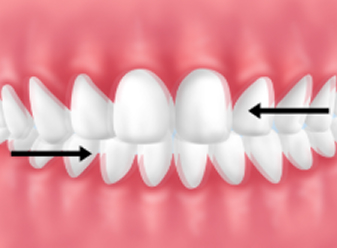

│グラインディング(歯ぎしり)

│クレンチング(食いしばり)